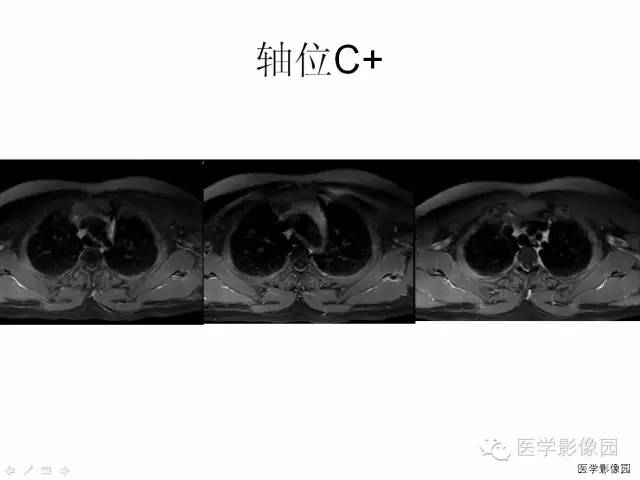

MRI是SSEH最有效的诊断方法,易于发现微小的出血灶,可以准确反映病灶的大小、形态、部位及与周围组织的关系;

根据病变的信号不同,可与炎症和肿瘤等病变相鉴别,明确血肿性质及推断出血时间,鉴别血肿分期,结合临床表现决定治疗方案。

硬膜外脓肿、转移瘤和淋巴瘤与急性期的硬膜外血肿影像学表现很相似,增强扫描对于鉴别诊断非常重要。

脓肿周围脓壁可出现明显环行强化,转移瘤和淋巴瘤均表现为显著较均匀强化,而SSEH在急性期强化不明显; 硬膜下血肿在临床上出现的概率远低于SSEH,多位于脊髓的腹侧面,SSEH表现为脊髓受压,一般不包绕脊髓,而硬膜下血肿,可以包绕脊髓或马尾,由于不受硬膜限制,没有硬膜移位,表面常不规则;海绵状血管瘤由于反复出血可致含铁血黄素沉积,在T2W I上病灶周边可见低信号带,易与SSEH区别。